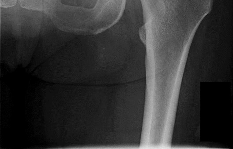

Question 2:

A 28-year-old male sustains a severe hyper-dorsiflexion injury to his ankle in a motor vehicle accident, resulting in a Hawkins Type III talar neck fracture. Which of the following arteries provides the predominant blood supply to the body of the talus, placing it at significant risk for avascular necrosis in this injury?

Correct Answer: Artery of the tarsal canal

Explanation:

The artery of the tarsal canal, which is a branch of the posterior tibial artery, provides the dominant blood supply to the talar body. In a Hawkins Type III fracture (talar neck fracture with subtalar and tibiotalar dislocation), the blood supply from the artery of the tarsal canal, the artery of the sinus tarsi, and capsular vessels are disrupted, leading to an avascular necrosis (AVN) rate approaching 100%.